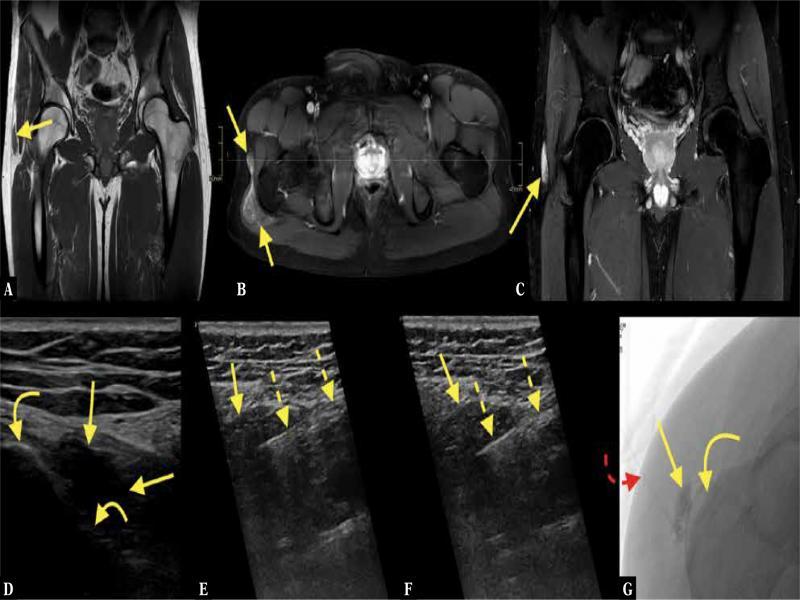

A 70-year-old patient with a history of malignant melanoma operated 3 years before presented with pain in the abdomen and right buttock. CT with intravenous contrast in the portal venous phase showed an intramuscular contrast-enhancing mass on the right ( A ; straight arrow – mass). MRI of the pelvis with intravenous contrast showed a solid contrast-enhancing tumor in the gluteal muscles ( B–E ). MRI and CT were unspecific, with a wide spectrum of differential diagnoses. The patient was referred for US-CNB ( F, G ; dashed arrows – biopsy needle, curved arrow – iliac bone). The histopathological diagnosis was extrapleural solitary fibrous tumor

Fig. 8.

A 28-year-old patient presented with a chronically swollen trochanteric region and more discomfort during the last weeks. There was a clinical suspicion of greater trochanteric bursitis. The patient was referred for MRI, where a solid lesion, not bursitis, in close relation to the greater trochanter, was detected ( A ; straight arrow – lesion). After intravenous contrast administration ( B, C ) there was vivid contrast enhancement. No muscle atrophy was visible. The MRI was unspecific, with a wide spectrum of lesions in the differential diagnosis. The patient was referred for US-CNB ( D–F ; curved arrows –greater trochanter, dashed arrow – biopsy needle). A histopathological diagnosis of a benign lesion, with a suspicion of vascular malformation, was made, and the patient was referred for intravascular treatment ( G ; red dashed curved arrow – catheter) which produced a good effect